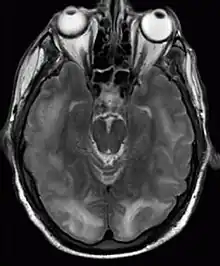

| Posterior reversible encephalopathy syndrome visible on magnetic resonance imaging as multiple cortico-subcortical areas of T2-weighted hyperintense (white) signal involving the occipital and parietal lobes bilaterally and pons. | |

The diagnosis is typically made with magnetic resonance imaging of the brain. The findings most characteristic for PRES are symmetrical hyperintensities on T2-weighed imaging in the parietal and occipital lobes; this pattern is present in more than half of all cases.[1][3] FLAIR sequences can be better at showing these abnormalities.[4] Some specific other rare patterns have been described: the superior frontal sulcus (SFS) watershed pattern, a watershed pattern involving the entire hemisphere (holohemispheric), and a central pattern with vasogenic oedema in the deep white matter, basal ganglia, thalami, brainstem and pons.[1][3] These distinct patterns do not generally correlate with the nature of the symptoms or their severity, although severe edema may suggest a poorer prognosis.[1] If the appearances are not typical, other causes for the symptoms and the imaging abnormalities need to considered before PRES can be diagnosed conclusively.[4] In many cases there is evidence of constriction of the blood vessels (if angiography is performed), suggesting a possible overlap with reversible cerebral vasoconstriction syndrome (RCVS). Diffusion MRI may be used to identify areas of cytotoxic edema caused by poor blood flow (ischemia) but it is not clear if this prognostically relevant.[1][4] Abnormal apparent diffusion coefficient is seen in about 20% of cases.[4]